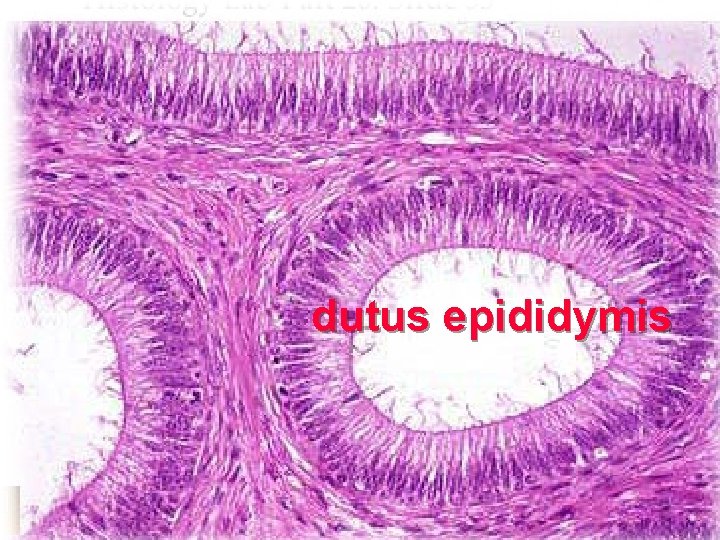

2. dutus epididymis l 4 -6 m,highly convoluted l pseudostratified ciliated columnar Epi. =principal C + basal C l lumen is regular,filled with sperm & secretions l the proximal , efferent ductules; the distal, ductus deferens.

dutus epididymis